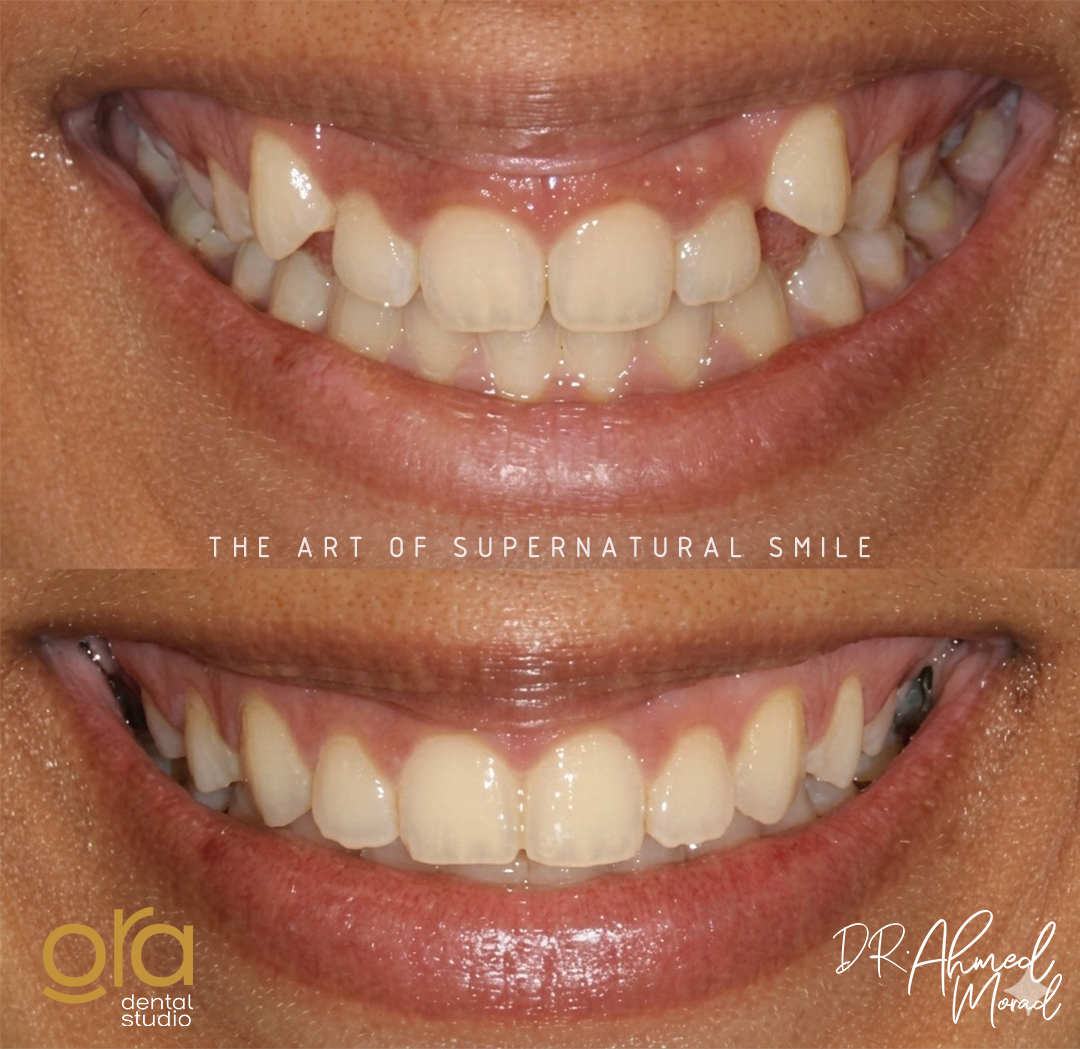

تقويم الأسنان

ابتسامتك المثالية تبدأ من انتظام أسنانك وتناسقها، وهذا ما نحرص عليه في ORA Dental Studios. فالتقويم ليس مجرد إجراء جمالي وحسب، بل هو علاج متكامل يعيد لأسنانك موقعها الصحيح ويحافظ على صحة فمك ولثتك. بفضل تقنيات التقويم الحديثة، أصبح بإمكانك الحصول على ابتسامة جذابة ووظيفة فموية سليمة بسهولة وراحة، مع نتائج تدوم لسنوات طويلة.

تقويم الأسنان في ORA Dental هو إجراء علاجي وتجميلي يهدف إلى تصحيح وضعية الأسنان والفكين باستخدام أجهزة متخصصة، سواء كانت معدنية تقليدية، أو خزفية جمالية، أو تقويم شفاف غير مرئي. يعمل التقويم على تحسين تناسق الأسنان، وتسهيل عملية المضغ والنطق، والحفاظ على صحة الفم والأسنان على المدى الطويل.

تقويم الأسنان لا يمنحك ابتسامة متناسقة فحسب، بل يحسن وظائف الفم ويقيك من العديد من المشكلات الصحية مستقبلًا. ومن أبرز مميزات تقويم الأسنان:

- تحسين المظهر الجمالي للابتسامة.

- تصحيح تزاحم الأسنان واعوجاجها.